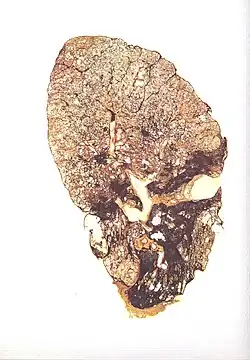

| Slice of a lung affected by silicosis | |